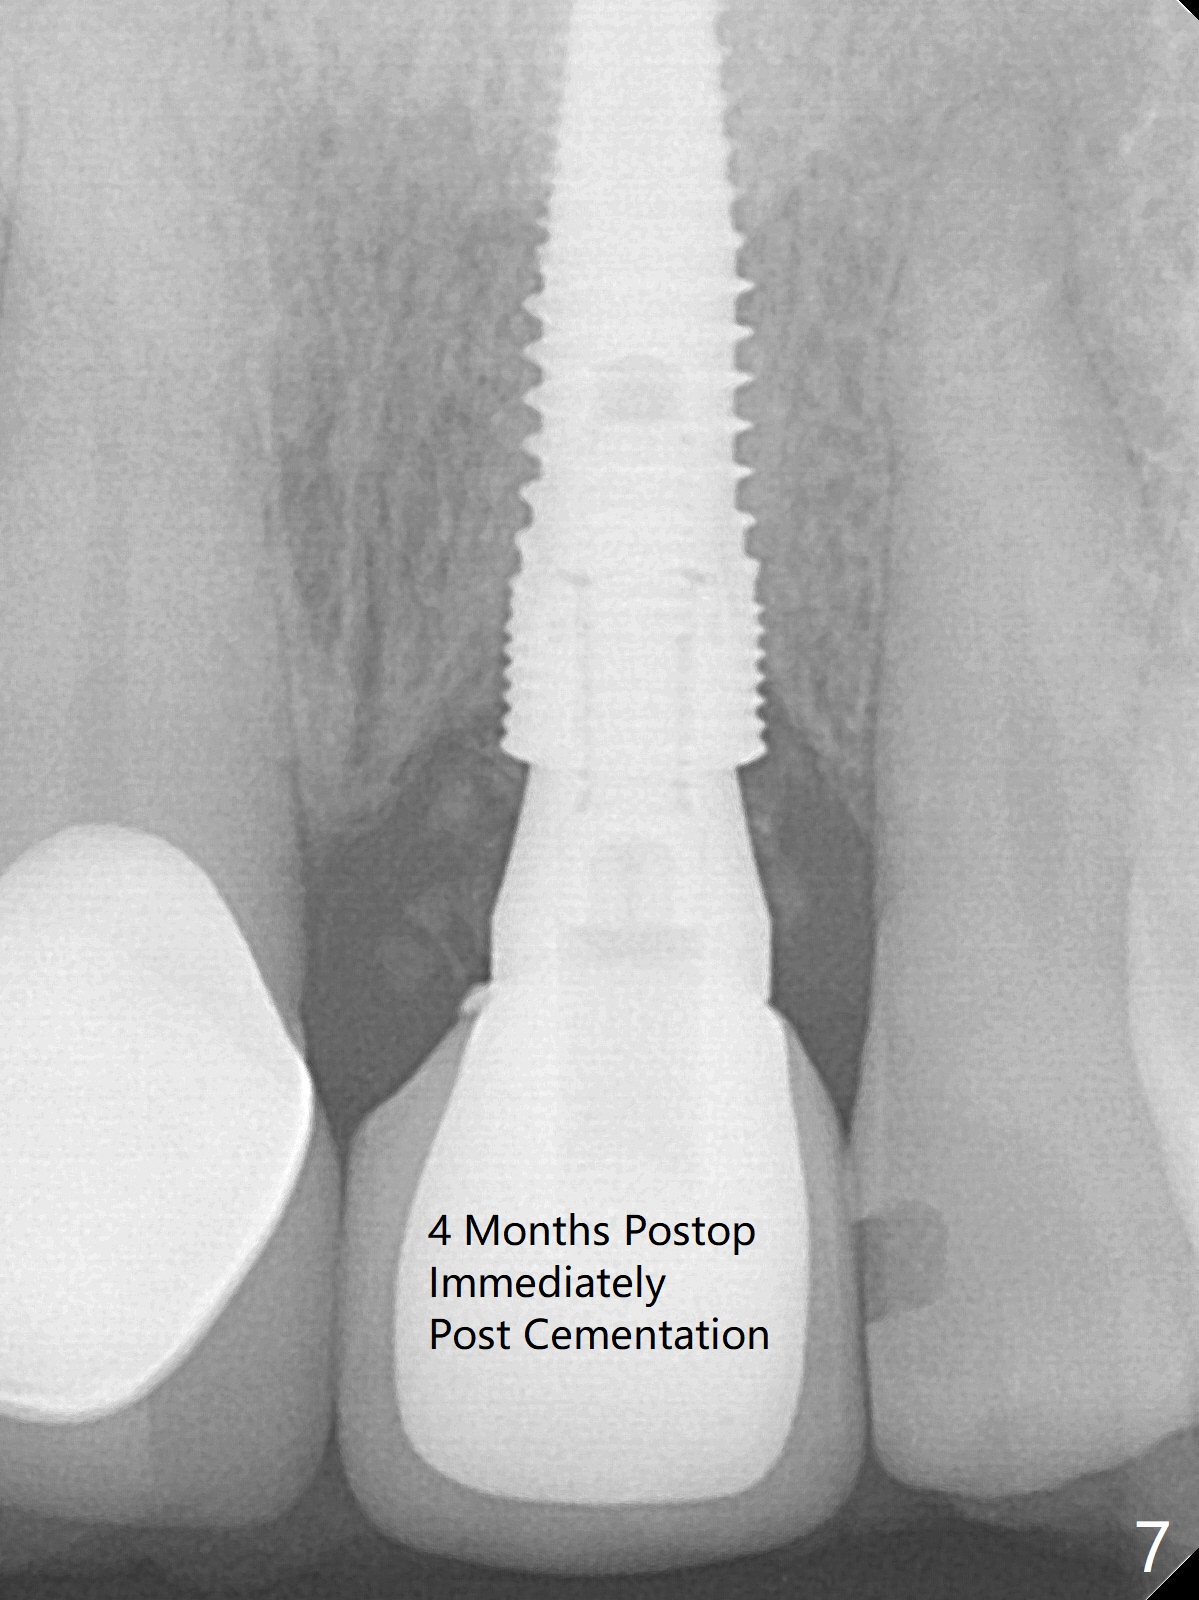

The buccal plate at #9 remains intact in spite of difficult extraction. Osteotomy is initiated in the palatal slope of the socket (Fig.1). The latter looks large when osteotomy is finished for a 3.8 mm implant. Without further osteotomy, a 4.5x14 mm SM implant is placed with primary stability (Fig.2). Without much attention, the coronal end of the bone-level implant is gradually deviated buccal, although the buccal gap is still 2 mm. An angled abutment is used (Fig.2); the future access hole is also buccal. Screw retention is impossible for cosmetic reason (Fig.3). To keep the access incisal and palatal, keep removing palatal bone sequentially. Or start osteotomy in the mid point of the palatal slope and keep the coronal end of the trajectory (Fig.5 pink line) palatal to the imagined incisal edge (Fig.4 white outline). The implant should be small (3.5 mm instead of 4.5 mm) so that it is easy to change the trajectory. The bone graft seems to have disappeared 3.5 months postop; the implant appears to have not been placed deep enough (Fig.6). In fact the implant plateau is < 2 mm subgingival palatal. An anterior immediate implant should be placed deep to reduce periimplantitis. There is reduced risk associated with abutment screw loosening, as compared to the posterior. Luckily the patient has used water pik since implant placement. On the other hand, water pik may be related to loss of bone graft. Therefore, water pik should be used 1 month post bone graft associated with immediate implant. The bone graft remains around the abutment cuff 4 months postop (Fig.7; immediately post cementation).